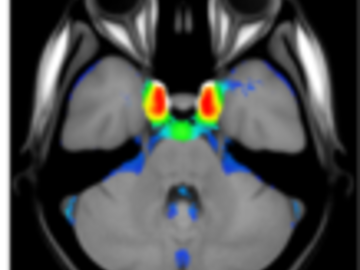

A statistical atlas of cerebral arteries

Magnetic resonance angiography (MRA) can capture the variation of cerebral arteries with high spatial resolution. These measurements include valuable information about the morphology, geometry, and density of brain arteries, which may be useful to identify risk factors for cerebrovascular and neurological diseases at an early time point. However, this requires knowledge about the distribution and morphology of vessels in healthy subjects. the statistical arterial brain atlas described in this work is a free and public neuroimaging resource that can be used to identify vascular morphological changes. The atlas was generated based on 544 freely available multi-center MRA and T1-weighted MRI datasets. the arteries were automatically segmented in each MRA dataset and used for vessel radius quantification. The binary segmentation and vessel size information were non-linearly registered to the MNI brain atlas using the T1-weighted MRI datasets to construct atlases of artery occurrence probability, mean artery radius, and artery radius standard deviation. This public neuroimaging resource improves the understanding of the distribution and size of arteries in the healthy human brain.

The statistical atlas consists of four image files in the niftii format and in MNI reference space (0.5 mm^3). These files include the TOF MRA average atlas (tofAverage.nii.gz), the vessel probability atlas (vesselProbabilities.nii.gz [in %]), the mean artery radius atlas (vesselRadius.nii.gz [in mm]), and the standard deviation of the artery radius atlas (vesselRadiusStd.nii.gz [in mm]). All images are saved using float values. The TOF MRA and T1-weighted datasets used for atlas generation can be downloaded from the original sources.

Time of flight atlas Probabilistic vessel atlas Radius vessel atlas (average) Radius vessel atlas (standard deviation)Publication: